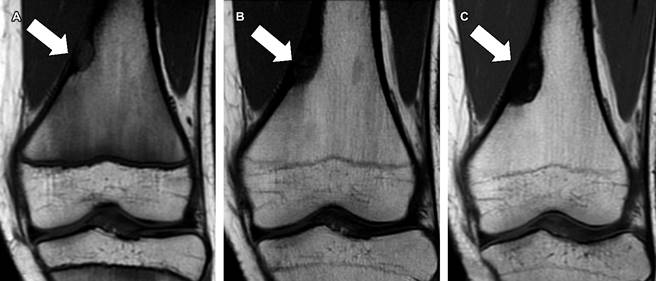

A la exploración física existe leve dolor a la palpación en la cara medial de ambos muslos. Se realizó resonancia magnética a nivel de ambas rodillas (Figuras 1B y 2C), en la cual se confirmó la presencia de fibroma no osificante en ambas rodillas, además se comparó con estudios previos del 2020 (Figura 2A) y 2022 (Figuras 1A y 2B).

En este paciente, es de interés la existencia de dos fibromas no osificantes, uno en cada fémur (Figuras 1 y 2), además del dolor que llega a limitar su actividad física, lo cual podría estar en relación con el crecimiento progresivo que han tenido las lesiones: en el fémur derecho en el 2022 (Figura 1A) la lesión medía 2.4 × 1.1 cm en sus ejes mayores y en el 2024 (Figura 1B) mide 3.3 × 1.9 cm; en el fémur izquierdo en el 2020 (Figura 2A) la lesión inicialmente detectada tenía dimensiones de 1.3 × 0.8 cm, en el 2022 (Figura 2B) con medidas de 3 × 1 cm y en el 2024 (Figura 2C) con ejes mayores de 3.5 × 1.2 cm.